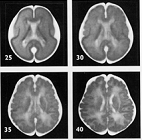

Nowoczesne metody diagnostyki medycznej pozwalają na uzyskanie szczegółowego obrazu narządów wewnętrznych pacjenta. Na ilustracji poniżej przedstawiono obraz mózgu człowieka w 25., 30., 35. i 40 tygodniu życia płodowego. Zdjęcia nie są w tej samej skali.

Można natomiast pozytywnie zweryfikować stwierdzenie 2. Ilustracja dość wyraźnie przedstawia stopniowe przejście od struktury stosunkowo prostej, o dużych gładkich powierzchniach (25.tydzień) do mocno pomarszczonej i wewnętrzne złożonej (40. tydzień). Stwierdzenie 2 jest zatem dość łatwo obronić. Można przypuszczać, że spośród badanych absolwentów, odpowiedzi niepoprawnej udzielili ci, którzy nie wiedzieli, czym jest kora mózgowa lub nie potrafili jej rozpoznać na zdjęciach.